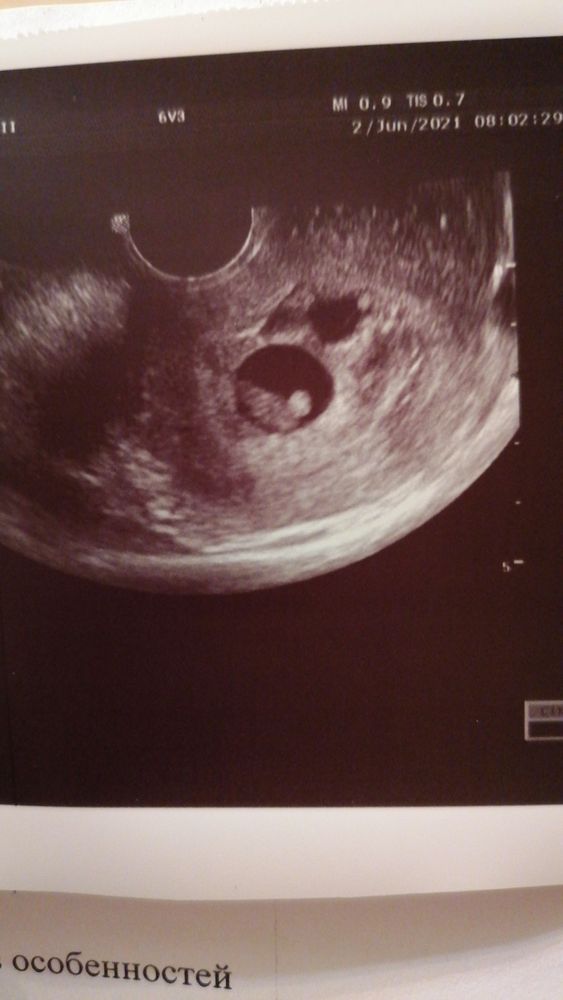

УЗИ 7 недель

Всё о нашей беременностиВсем привет! Сходила на УЗИ 7+2. Несостоявшаяся двойня, в одном есть эмбрион, послушали сердечко ❤️. На следующей неделе пойду вставать на учёт.

Второе яйцо выросло синхронно с первым, но абсолютно пустое, даже ЖМ не появилось (хотя на фотке есть какая то точка), но я надежд не питаю, главное что бы здоровому малышу не помешало. Выделений и болей никаких нет, сегодня как то резко ухудшился токс, мутит постоянно и ничто не спасает, а вечером вообще вырвало. Пока держусь, следующую неделю отработаю и на удаленку.

Фото УЗИ прикладываю, может кто подскажет, что за точка в правом эмбрион, на аппарате даже я увидела, что пусто, а тут вроде что то есть. У меня просто никогда не бывает, боюсь всего😁

ну у вас да, есть какая то точка в том, где нет эмбриона 🧐